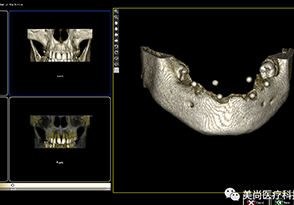

1.CT数据导入

2.成像预览

3.添加放射导板数据

5.种植模拟设计

6.自动生成报告及进行数据输出